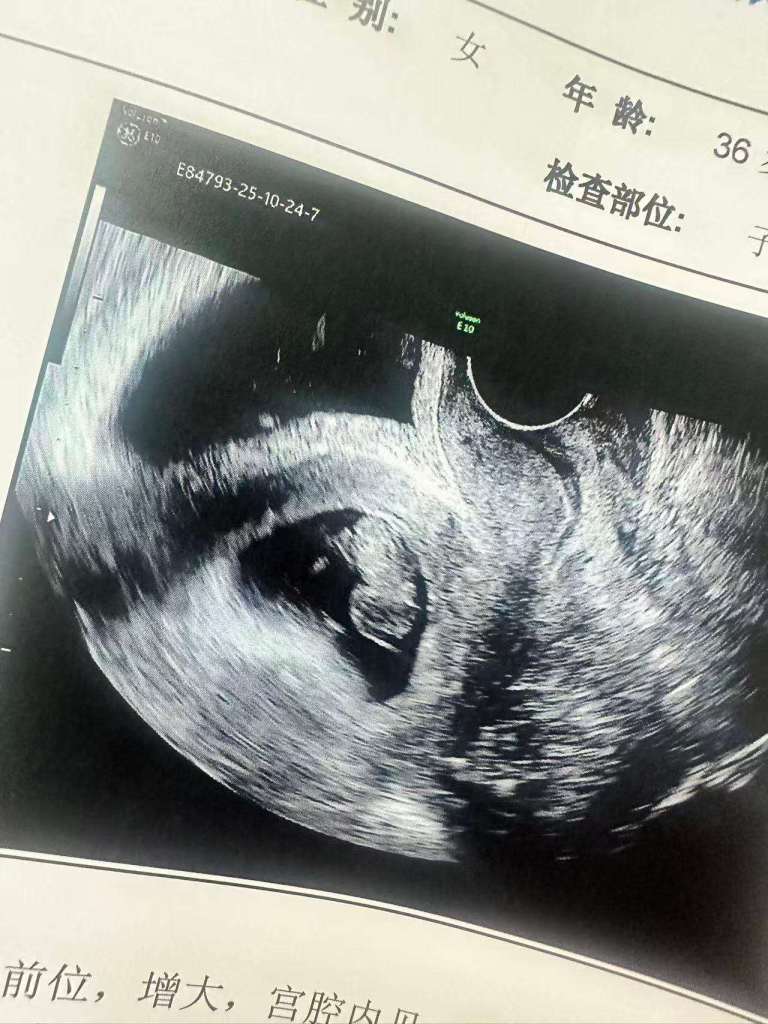

前天老婆去做了有一次检查,没问题的话就可以回来了。小花生还在顺利长大,在长胳膊腿了。